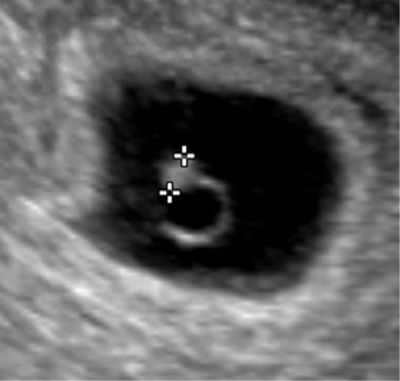

Embryon de 5 semaines et 4 jours. Dès ce moment, il est possible de visualiser le coeur de l'embryon et de l'enregistrer en écho-doppler.